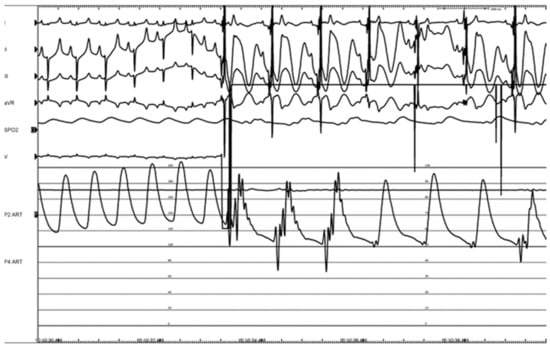

3.2. Canine Study—Ablation Efficacy